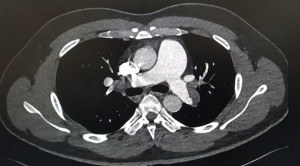

• Analisis Guideline Emboli Paru dari European Society of Cardiology 2019

Analisis Guideline Emboli Paru dari European Society of Cardiology 2019

Di tahun 2019, European Society of Cardiology (ESC) mengeluarkan guideline terbaru untuk diagnosis dan tata laksana emboli paru. Guideline ini bertujuan untuk membantu tenaga medis memilih strategi manajemen...(Baca Selengkapnya)

• Penggunaan Sistem Skoring pada Emboli Paru

Penggunaan Sistem Skoring pada Emboli Paru

Penggunaan sistem skoring pada emboli paru merupakan pemeriksaan alternatif yang lebih aman dan memiliki akurasi yang baik dalam diagnosis emboli paru. Diagnosis...(Baca Selengkapnya)